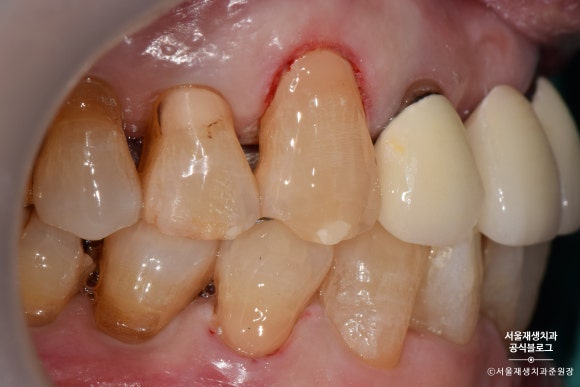

글라스아이오노머로 치경부마모증 치료하기

레진에 비해 자연스러움이나 수명은 약간 부족하지만,

저렴한 가격에

치경부마모증의 치료를 위한

최소한의 자격요건을 갖춘 기특한 재료입니다.

글라스아이오노머로 치료를 시작해보겠습니다.

며칠 후 글라스아이오노머 치료를 위해 다시 방문해주셨습니다.

그 사이 감쪽같이 아문 잇몸이 보이시나요?^^

글라스아이오노머를 이용한 치료도

레진과 마찬가지로 치아의 표면을 깨끗하게 소독하는 것으로 시작합니다.

글라스아이오노머를 위한 전처리제를

치아표면에 도포합니다.

글라스아이오노머를 치아 표면에 도포합니다.

밀가루 반죽같은 것을 기구를 대고 꾹~ 눌러주거나,

시린지 형태로 된 제품으로 짜넣는 방법 등이 있습니다.

5분 정도의 시간이 지나고

글라스아이오노머가 제법 단단해졌습니다.

글라스아이오노머의 표면을 부드럽게 다듬어봅니다.

레진과 비교했을 때 약간 혼탁한 색감, 부자연스러운 느낌은 있지만,

후방치아 치료용으로는 손색이 없습니다^^